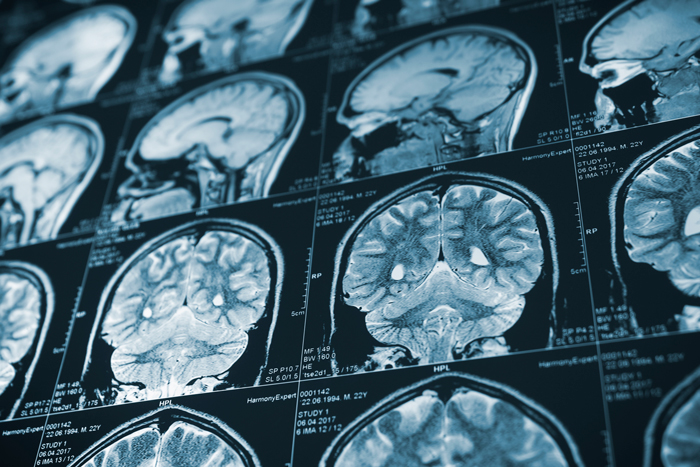

La tomografía computarizada, como parte de las pruebas de imagenología, es una herramienta fundamental para que un médico pueda hacer un diagnóstico, especialmente cuando se tratan de padecimientos relacionados con el cerebro y la columna vertebral.

Más detallada que una prueba de rayos X, la tomografía permite ver el interior del cuerpo gracias a una combinación de la técnica ya mencionada y una computadora, creando imágenes de los órganos, los huesos y otros tejidos. Hoy en día, la prueba es sumamente común, pero ¿qué le dice exactamente, en este caso, a un neurocirujano? Lo detallamos en el siguiente artículo.

La tomografía utiliza rayos X para producir imágenes de los órganos, los huesos y los tejidos. Esta ayuda a llegar a un diagnóstico adecuado al mostrar el área del cerebro que está afectada. Generalmente, se usa para detectar rápidamente una hemorragia cerebral y para determinar si alguien que ha sufrido un derrame puede recibir tratamiento intravenoso para disolver los coágulos de forma segura.

También se emplea para detectar irregularidades óseas y vasculares, tumores cerebrales y quistes, daño cerebral producto de lesiones en la cabeza o epilepsia, hidrocefalia y otros desórdenes.

Después, los datos son procesados y se muestran como imágenes de corte transversal de las estructuras de los órganos.